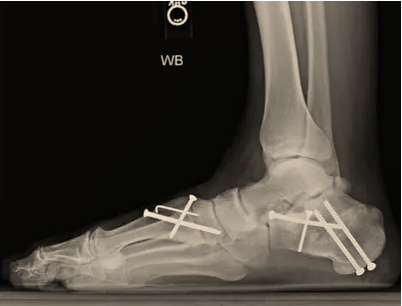

Deformity Correction Cavus Foot Reconstruction Cavus Foot Reconstruction Triple Fusion Triple Fusion Charcot Beaming Charcot Beaming Double Fusion Double Fusion Flatfoot Reconstruction Flatfoot Reconstruction Subtalar Fusion Subtalar Fusion